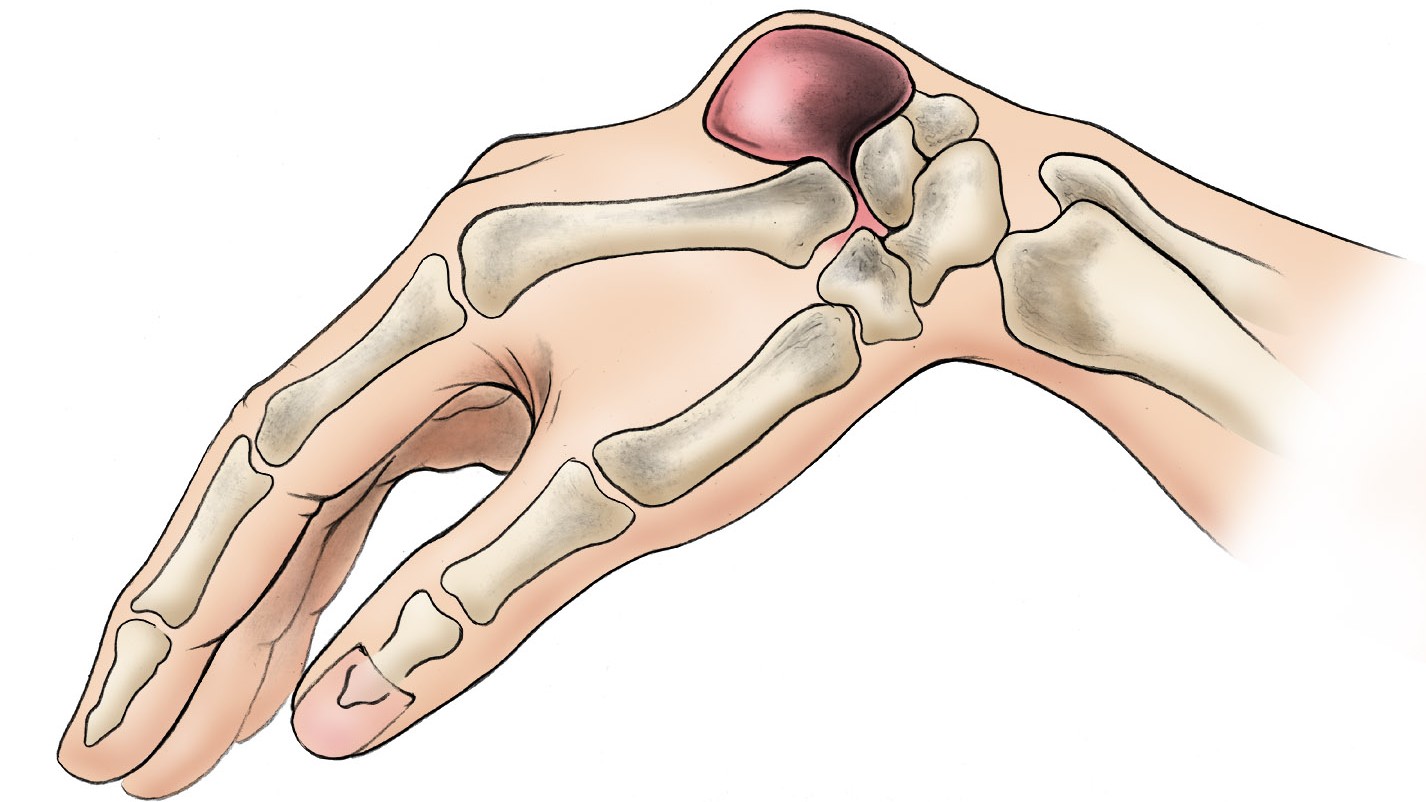

Siddarth Kamath K, Jayakrishnan KN, Acharya A, Bhat AK. 'Vanishing carpal bones' in a patient with congenital adrenal hyperplasia - A diagnostic dilemma. J Orthop. 2020;22:493-496.

www.researchgate.net/publication/344589487_Vanishing_carpal_bones'_in_a_patient_with_congenital_adrenal_hyperplasia_-_A_diagnostic_dilemma